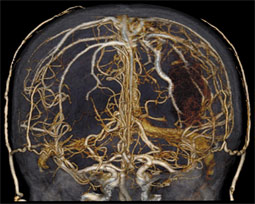

This scan, which took only 4 seconds, shows the blood vessels inside the brain. Such detail helps physicians diagnose strokes, aneurysms (including one visible on the right side of this image), brain tumors and more.